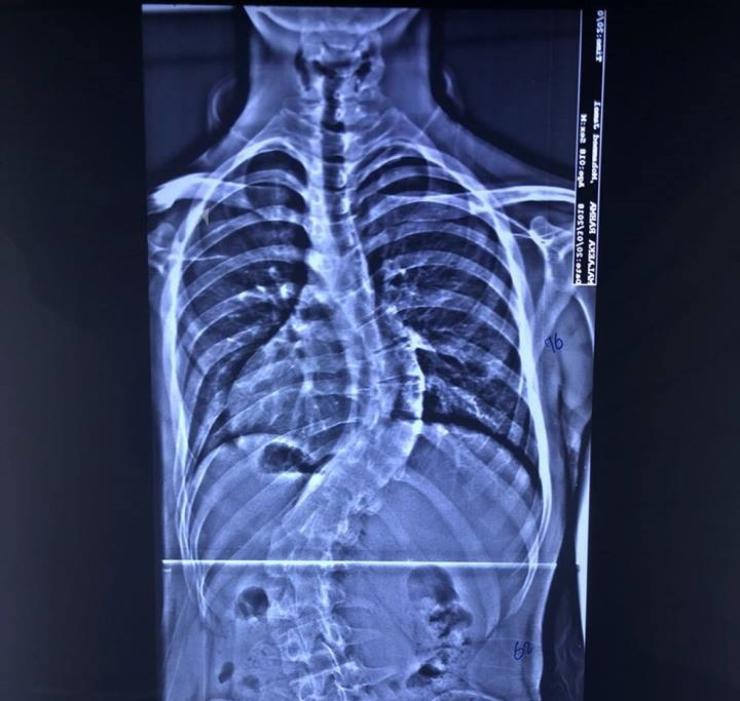

أعلن فريق طبي بمستشفى الكفيل التخصصي نجاحه بعملية تعديل إعوجاج العمود الفقري (سكوليوسز) لطفل بعمر سبعة أعوام، فيما أشاد ذوو الطفل بتكفل المستشفى بإجراء العملية بشكل مجاني. وقال رئيس الفريق الطبيب السوري، د. وائل قاسم اختصاصي جراحة العمود الفقري، ان فريقنا نجح بإجراء عملية لطفل بعمر سبعة أعوام يعاني من اعوجاج العمود الفقري (سكوليوسز). مبيناً "ان العملية إستغرقت قرابة الـ(9) ساعات واجريت بتقنيات طبية حديثة وفرها المستشفى، وإستعاد الطفل إستقامة عموده الفقري بشكل جيد. من جانبه قال والد الطفل ويدعى (م ـ ج)، ان المستشفى تكفل بإجراء العملية لولدي بشكلٍ مجاني بعد أن وجهت مناشدة لإدارته وتمت الإستجابة لي سريعاً. معرباً عن شكره للمستشفى لما يقدمه من خدمات مجانية للمرضى المحتاجين من مختلف محافظات البلاد، ومساهمته بمعالجة المرضى الذين لا يملكون ثمن العلاج وغير قادرين على السفر للعلاج في الدول الإخرى. يذكر أن واردات المستشفى تذهب بالكامل لتمويل خدماتها التشغيلية - ومنها رواتب العاملين - ولرعاية المرضى الفقراء، إذ أن ارتفاع أسعار العمليات هو بسبب ارتفاع سعر الأجهزة المتطورة والتي تضاهي ما موجود عالمياً وهي تتطلب ادامة مستمرة، وهذا يحتاج مبالغ كبيرة. كما أن جميع العمليات التي تجرى في المستشفى يقوم بها أطباء متميزون ومختصون إزاء نسبة معينة من المبلغ الذي يدفعه المريض، وهم من العراقيين والمغتربين والاجانب من ذوي الخبرة والنجاحات العالمية. أما الجزء الثاني من مبلغ العملية الذي يدفعه المريض، فيذهب لتغطية رواتب العاملين والاطباء المقيمين والممرضين، وتغطية مصاريف المستشفى من الكهرباء والماء وخدمة المعامل الخدمية التابعة للمستشفى، وخدمات الجباية الحكومية، إضافة إلى تمويل تذاكر وتأشيرات واقامة وحماية الاطباء الاجانب المستقدمين من الخارج. وما يتبقى من حصة المستشفى يغطي مشروع (اطباء بلا اجور)، الذي يهدف لمساعدة المرضى الفقراء والحشد ومن كل الفصائل، ومشروع (التخفيض) الذي يتكفل إجراء العمليات لفقراء المرضى بشكل مجاني أو بتخفيض الكلفة لنصفها او ثلثها.